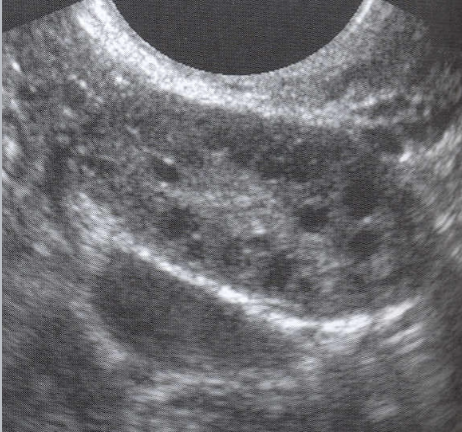

PCOS U/S appearance:

Bilateral enlargement

Contain multiple (12 or more), tiny peripheral cysts 2-9 mm

Ovarian volume >10 cm

25% of pt’s have normal appearing ovaries

The US appearance of PCOS may appear in women whose ovaries are treated with FSH

“String of Pearls” or “Black Pearl Necklace”